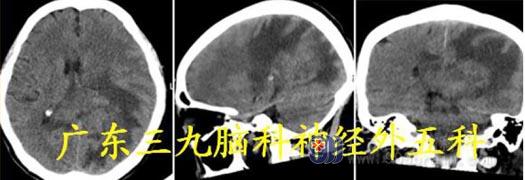

入院诊断:1.左侧枕叶、胼胝体尾部,左侧颞叶占位性病变;2.双肺多发间质性炎症;双肺泡性肺气肿。

头颅MR:胼胝体压部及左侧枕顶叶示一团片状占位性病变,增强后病变呈明显较均匀

强化,范围约为6.4cm×4.5cm×3.6cm,周围示片状长T1 长T2 水肿信号影。胼胝体压

部及左侧枕顶叶、左侧颞叶、双侧额叶多发占位性病变,考虑肿瘤性病变,淋巴瘤可能。

头颅CT:胼胝体压部及左侧颞枕顶叶占位性病变呈偏等密度为主。

术后放疗后复查MR:左侧枕顶叶病灶部分切除术后改变,胼胝体压部及左侧枕顶叶残

留病灶范围较前缩小,强化范围较前缩小。

术后病理:原发性中枢弥漫大B 细胞性淋巴瘤,GCB 型,WHO IV 级。